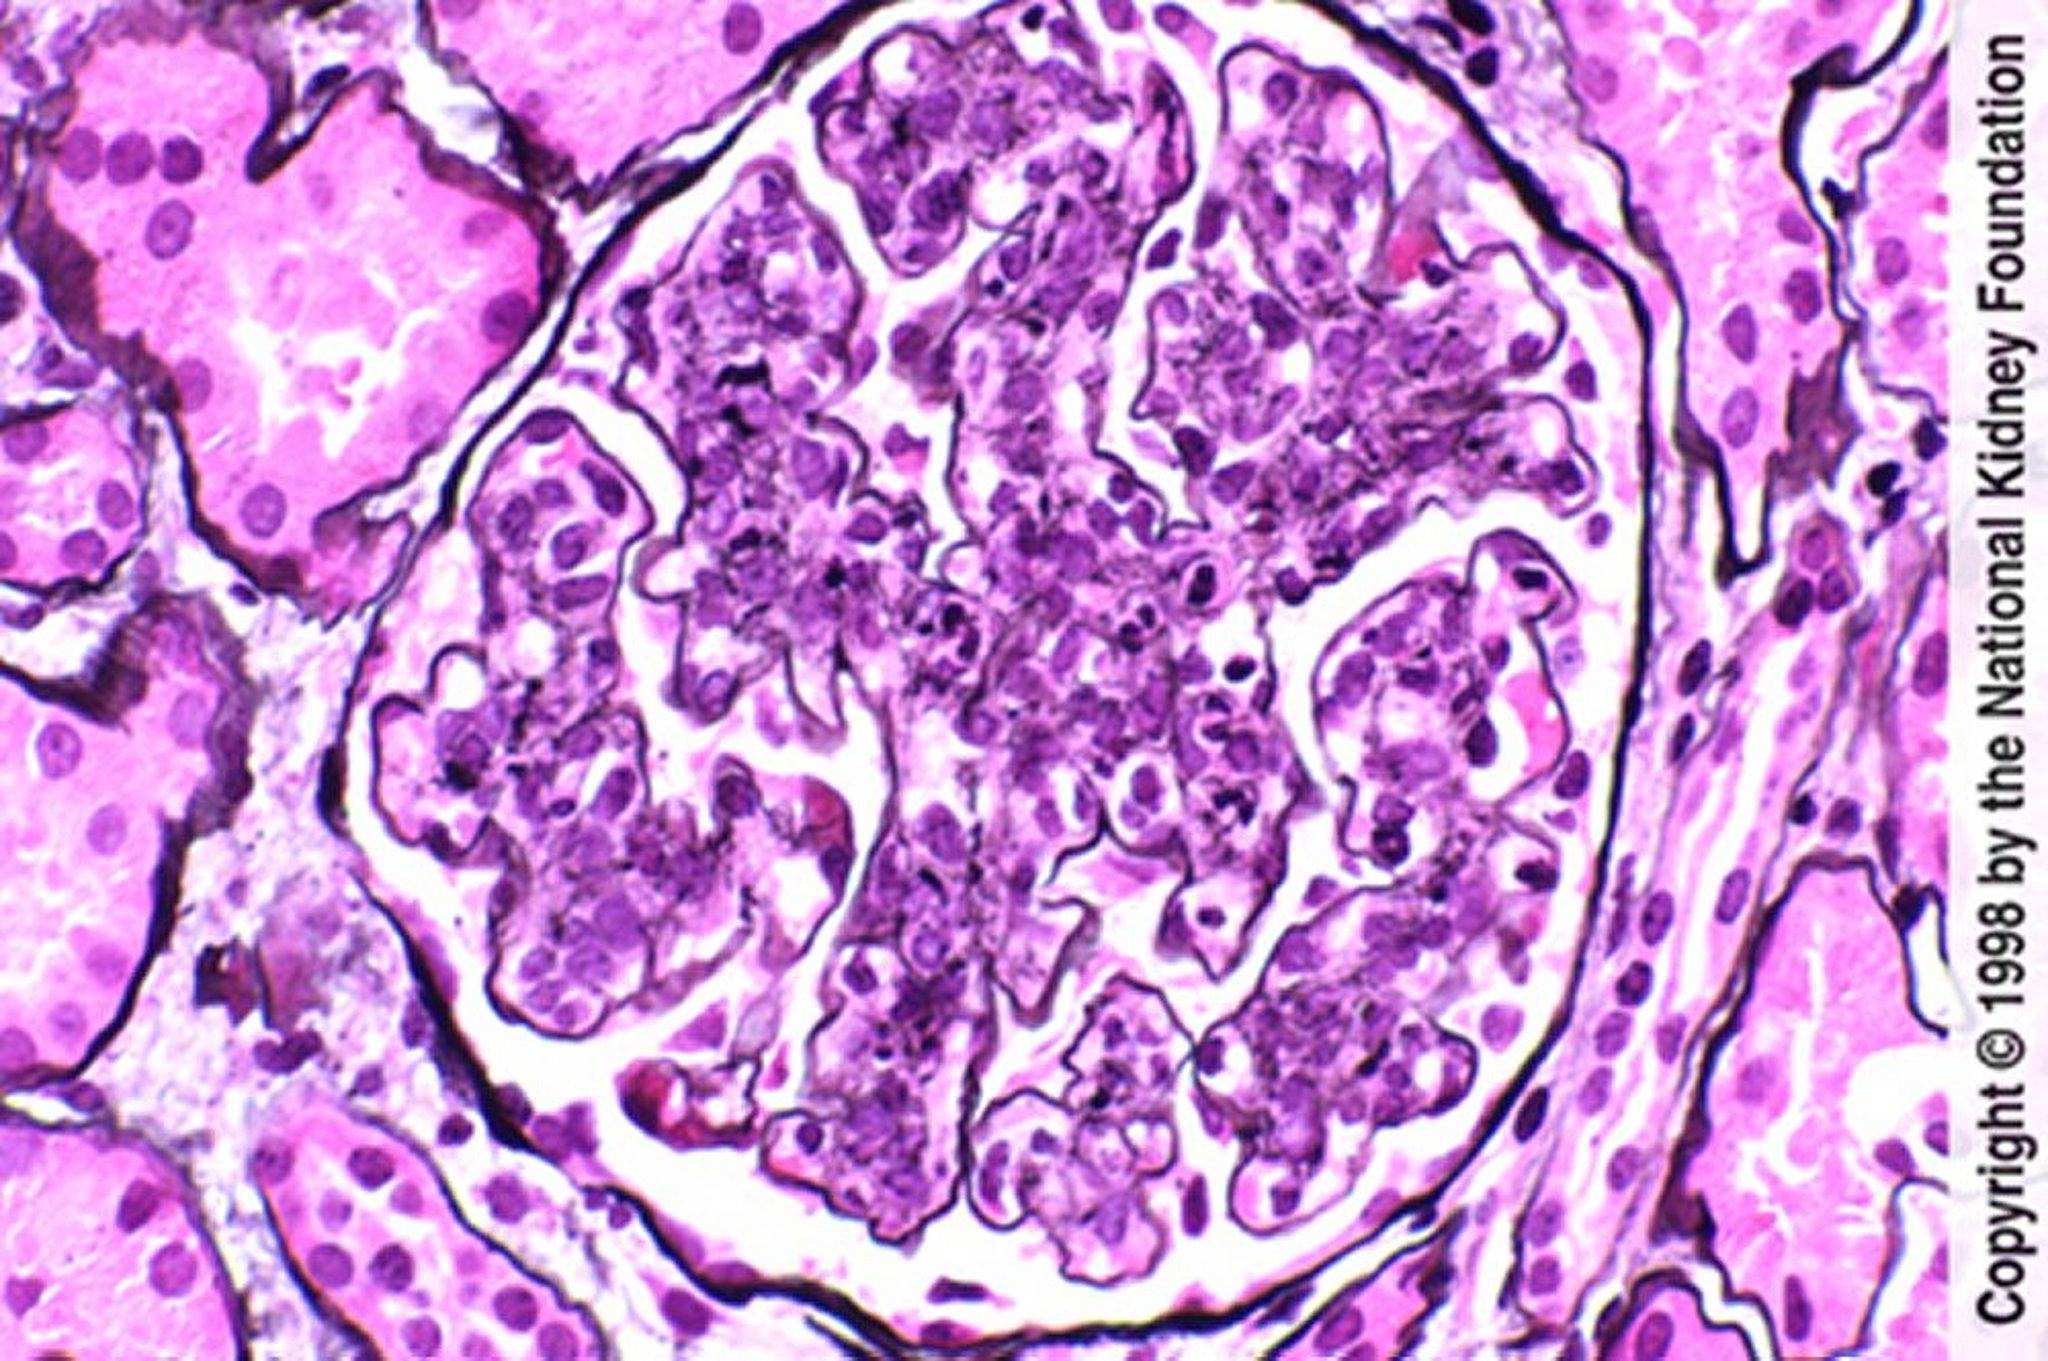

Postinfektiöse Glomerulonephritis (Hyperzellularität mit neutrophiler Infiltration)

Hyperzellularität von Endothel und Mesangium mit neutrophiler Infiltration (Jones-Silberfärbung, ×400).

Image provided by Agnes Fogo, MD, and the American Journal of Kidney Diseases' Atlas of Renal Pathology (see www.ajkd.org).